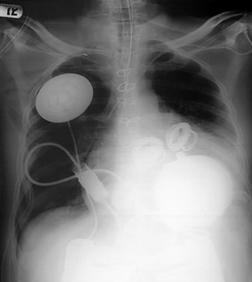

In fig.6 se prezinta o radiografie a unui pacient implantat cu inima artificiala :

Fig. 6